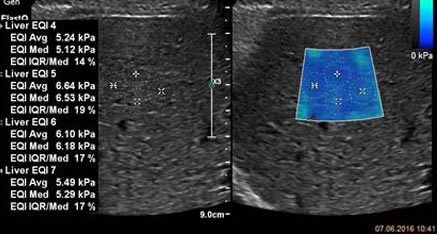

Известно, что результаты ультразвуковой количественной оценки степени жесткости печени зависят от производителя. Понимая эту проблему, компания Philips прикладывает все усилия чтобы клиническое сообщество получало самую точную и клинически достоверную информацию.  При партнерстве с Российской ассоциацией специалистов ультразвуковой диагностики в медицине и ведущими экспертами кафедры ультразвуковой диагностики Университета Павии (Италия) были подготовлены рекомендации с целью стандартизации оценки жесткости печени на ультразвуковом оборудовании компании Philips

Рекомендации РАСУДМ по проведению эластографии сдвиговой волной для оценки жесткости печени при использовании ультразвуковых аппаратов компании Филипс с примером протокола

Клинические изображения различных стадий фиброза печени

Изучите клинические примеры неинвазивной оценки фиброза печени.

Эластография

Новые возможности эластографии в сочетании с превосходным качеством изображений позволяют использовать менее инвазивные и менее дорогостоящие методы получения данных при диагностике заболеваний печени.